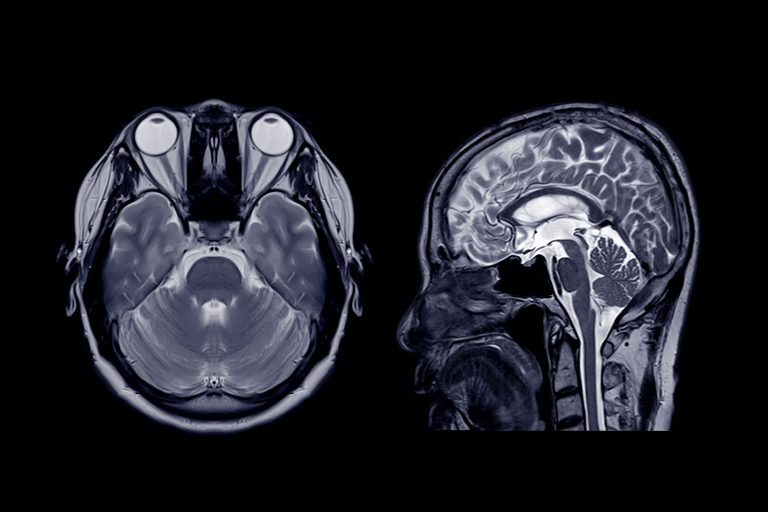

MRT

Die Magnetresonanztomographie (MRT) ist ein modernes, strahlungsfreies Bildgebungsverfahren, das vollständig ohne Röntgenstrahlen auskommt. Sie eignet sich in besonderem Maße zur detaillierten Darstellung von Weichteilstrukturen wie Gehirn und Rückenmark, Sehnen und Muskeln, Bandscheiben sowie inneren Organen wie Leber, Nieren, Bauchspeicheldrüse und Milz. Darüber hinaus lassen sich auch knöcherne Strukturen wie Wirbelkörper und Gelenke sowie deren Bestandteile…